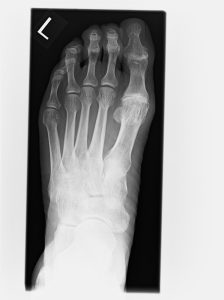

- Röntgen zur Beurteilung von Gelenkspalt, Osteophyten, Stellung

| Stadium | Typische Befunde | Beweglichkeit Großzehe | Röntgen-Hinweise | Geeignete Behandlung |

|---|---|---|---|---|

| Frühstadium („limitus“) | zeitweilige Abrollschmerzen, Reizung, kleiner Knochenrand | eingeschränkt, noch vorhanden | erste Osteophyten, Gelenkspalt erhalten | Schuh-/Einlagenversorgung (Rocker-Sohle), Physio; evtl. Cheilektomie |

| Mittleres Stadium | häufigere Schmerzen, tastbarer Knochenrand, Druckstellen | deutlich eingeschränkt | Osteophyten + Verschmälerung des Gelenkpaltes aber noch 50 % des Gelenkspalt erhalten | Konservativ wie oben; je nach Ziel Cheilektomie ± Moberg-Osteotomie Youngswick Operation |

| Fortgeschritten („rigidus“) | Schmerzen auch in Ruhe, deutlich steifes Gelenk | stark eingeschränkt bis kaum möglich | deutliche Gelenkspaltminderung/-aufhebung, ausgeprägte Osteophyten | Arthrodese (Versteifung) als zuverlässige Lösung; Endoprothese selektiv |